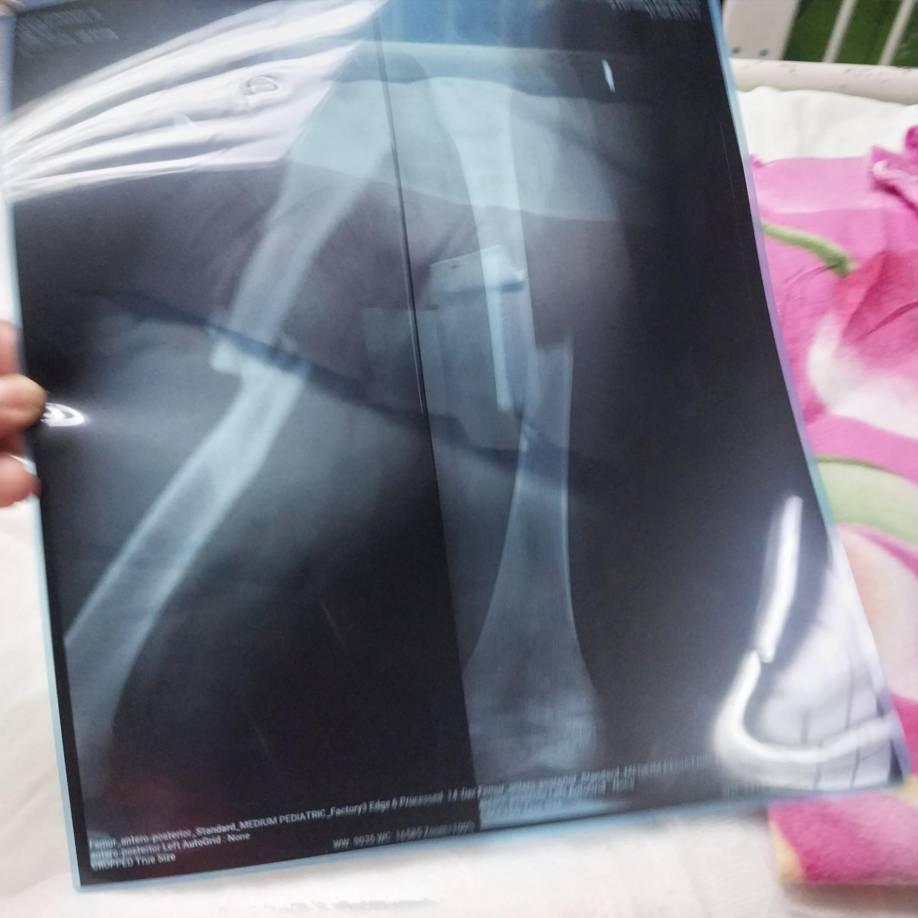

5 / 14La pequeña Fernanda fue trasladada grave a un centro hospitalario en donde llevaba sus dos piernas fracturadas.

6 / 14Rayos x de las dos piernitas de Fernanda, quien tuvo que pasar su cumpleaños cinco, el sábado 21 de diciembre, en un hospital.